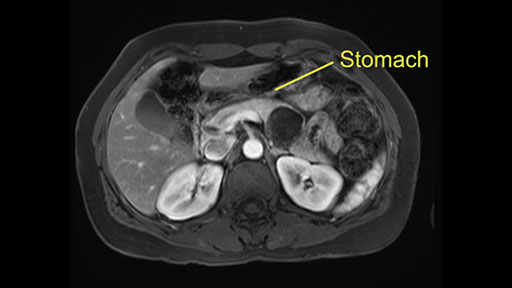

In terms of maintenance of the regular planes, other factors that we need to consider is whether you need to enter in posteriorly to Gerota’s fascia to obtain an adequate margin and anteriorly to ensure the tumor can be mobilized safely off of the posterior wall of the stomach.

So first step that we do: mobilize the splenic flexure first to visualize Gerota’s fascia and that would help bring down the colon and expose the pancreatic tail. So now that the pancreas is visible, division of the gastrocolic ligament will come into view. And a window can be created at the inferior edge of the pancreas to slowly lift the inferior edge to expose the splenic vein behind. This is the slow-down moment that I am talking about because the MR shows that there could be contact with the cyst. It’s important to know that to avoid perforation, to avoid rupture of the cyst, because we need to avoid touching the cyst, it is quite a size of 4.3 about 4cm.

So at this point, something that would be very helpful is to use gravity so that we can perhaps position the patient by moving the head down a little bit so that we can lift the pancreas and allow the stomach to retract superiorly, so we don’t have to retract the stomach with another instrument.